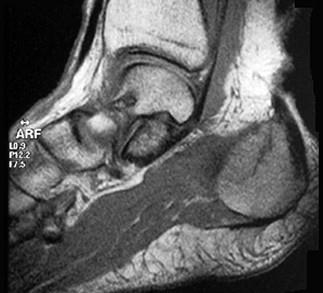

女,48岁,長跑运动员,左跟骨部痛,结合图像,最可能的诊断是 ( )A、左踝关节退行性变B、应力性骨折C、左跟骨骨髄炎D、结核...

问题 女,48岁,長跑运动员,左跟骨部痛,结合图像,最可能的诊断是 ( )

选项 A、左踝关节退行性变 B、应力性骨折 C、左跟骨骨髄炎 D、结核 E、未见异常

答案 B